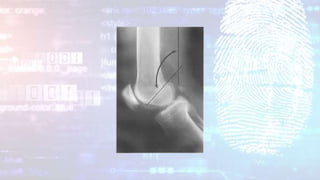

A: knee of premature newborn. The distal femoral and

proximal tibial epiphyses are not ossified. B: term

newborn with knee epiphyses (arrows) present

Forensic Radiology by B. G. Brogdon, M.D

A: knee ofpremature newborn. The distal femoral and proximal tibial epiphyses are not ossified. B: term newborn with knee epiphyses (arrows) present Forensic Radiology by B. G. Brogdon, M.D